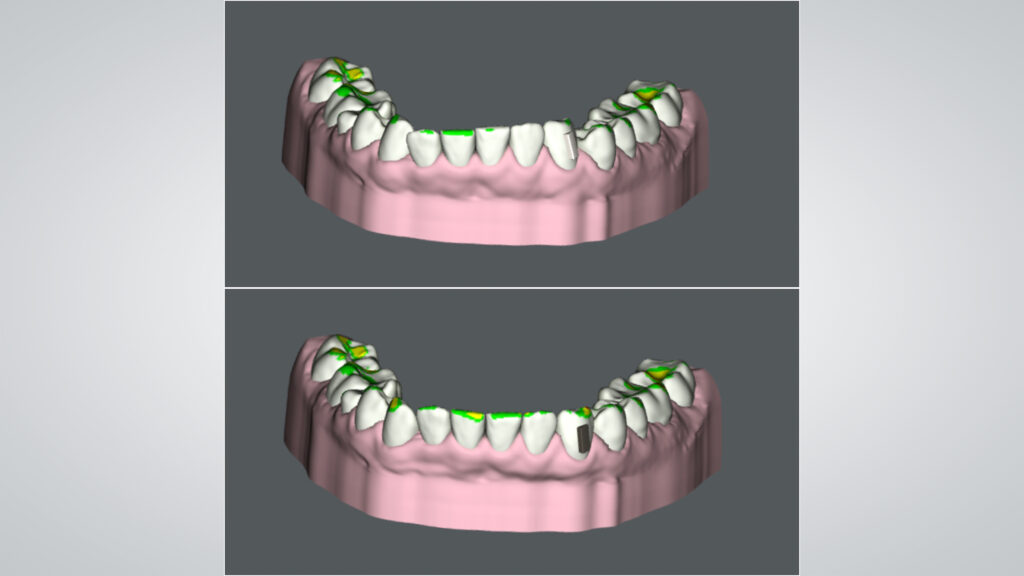

Im vorliegenden Fall wurde eine leichte extraorale Verschiebung der Mittellinie nach links festgestellt. Zudem zeigte die interkommisurale Linie eine Diskrepanz von links nach rechts. Bemerkenswert war die signifikante Volumendifferenz der rechten Lippenpartie im Vergleich zur linken. Zudem wurde eine Abweichung zwischen extraoraler und intraoraler Mittellinie identifiziert. Die klinische Befundung ergab einen Engstand im Oberkiefer, welcher als Rezidiv nach einer kieferorthopädischen Behandlung interpretiert wurde. Zusätzlich wurden ein Zahnschmelz-Chipping, eine Kunststoffverblendung am endodontisch vorbehandelten Zahn 11 sowie ein mild ausgeprägtes Gummy Smile diagnostiziert; insgesamt zunächst ein vergleichsweise einfacher Fall für ein Aligner-Bleaching-Veneers-Konzept. Aber: Obwohl der Fall auf den ersten Blick wie ein einfacher „Kandidat“ für ein Aligner-Bleaching-Veneers-Konzept wirkte, offenbarte eine detaillierte Untersuchung des Unterkiefers die volle Komplexität. Die Unterkieferfront zeigte eine blockartige Verschiebung. Während die rechte Seite intrudiert und nach bukkal protrudiert war, zeigte die linke Seite eine Extrusion und Retrusion (Abb. 4). Diese spezifische Konstellation erklärte die in der ästhetischen Analyse festgestellte Lippenposition. Ursache für die Situation war ein fehlerhaft positionierter Retainer. Der Retainer am rechten Eckzahn war vor Jahren abgebrochen. Das verursachte diese negative Entwicklung bei einer ansonsten positiven Retainer-Funktion. Die Blockbewegung des Unterkiefers musste auf diesen Umstand zurückgeführt werden.

Bevor wir mit der Planung der Behandlung beginnen konnten, benötigten wir einen detaillierten Fotostatus, eine Panorama-Röntgenaufnahme sowie einen digitalen Scan des Gebisses. Es war klar, dass eine initiale Korrektur mittels Alignern erfolgen musste, um den Okklusionsplan im Bereich der Frontzähne zu regulieren (Abb. 5 und 6). Die zeitliche Begrenzung stellte hierbei eine echte Herausforderung dar, denn das Zeitfenster ermöglichte nur zehn Aligner-Schienen pro Kiefer (SureSmile Aligner, Dentsply Sirona). Nach Anwendung der siebten Schiene, einem Zwischenscanning und der Modellherstellung war es für das zahntechnische Team an der Zeit, aktiv zu werden.